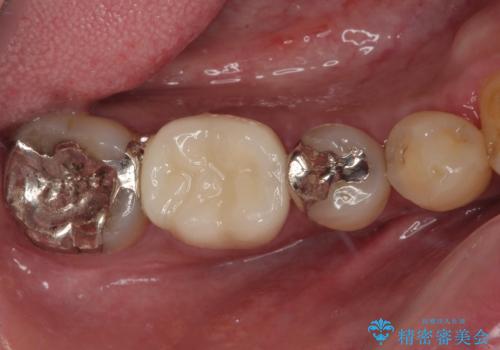

銀歯をセラミックにしたい オールセラミッククラウン

担当医 有澤哲郎